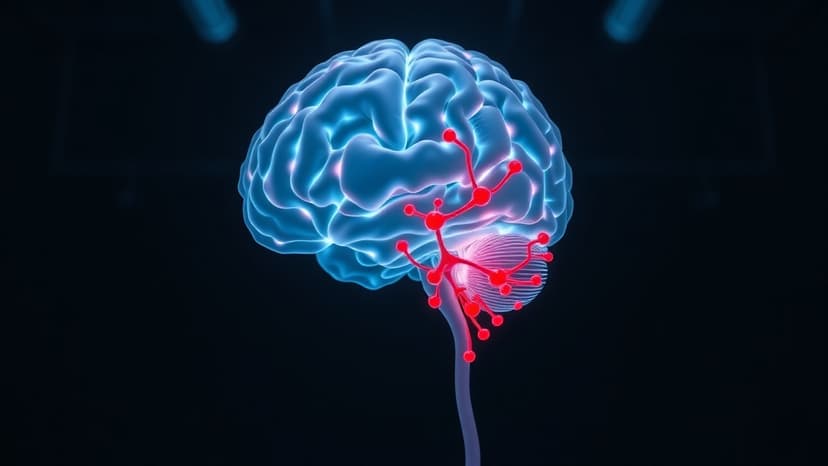

Pediatric neurosurgeons explained that infections can spread from the sinuses to the brain through the thin bone separating them, a rare but potentially fatal complication. The teen required two emergency surgeries to relieve pressure and combat the persistent infection.